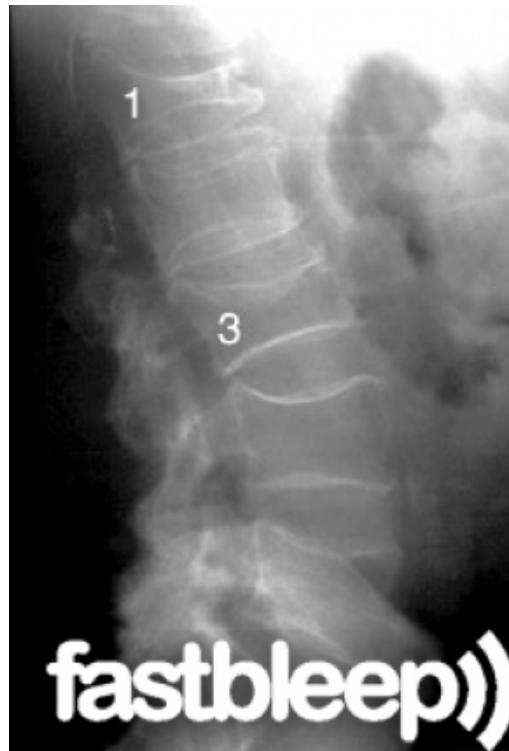

Degenerative Spondylolisthesis

- Definition: Common degenerative condition characterized by subluxation of one vertebral body anterior to the adjacent inferior vertebral body with intact pars

- Demographics: Most common in females over 40 years of age, at the L4-5 level

- Diagnosis: Lateral radiographs; flexion and extension lateral lumbar radiographs can identify degree of instability

- MRI: Helpful for central or foraminal stenosis

Treatment:

- Nonoperative: Trial with NSAIDs and physical therapy

- Surgical: Indicated for progressive disabling pain that has failed nonoperative management, and/or progressive neurological deficits